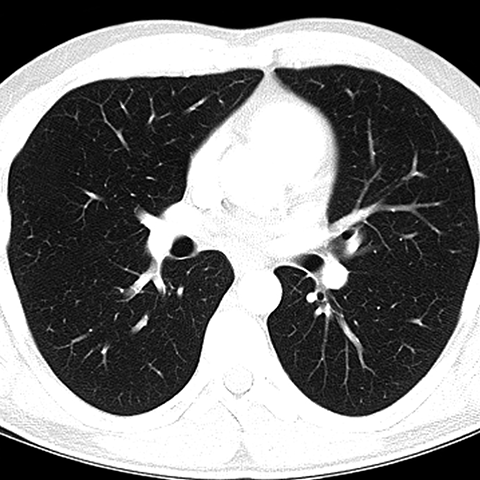

CT of Normal Trachea and Bronchi [4 of 5]